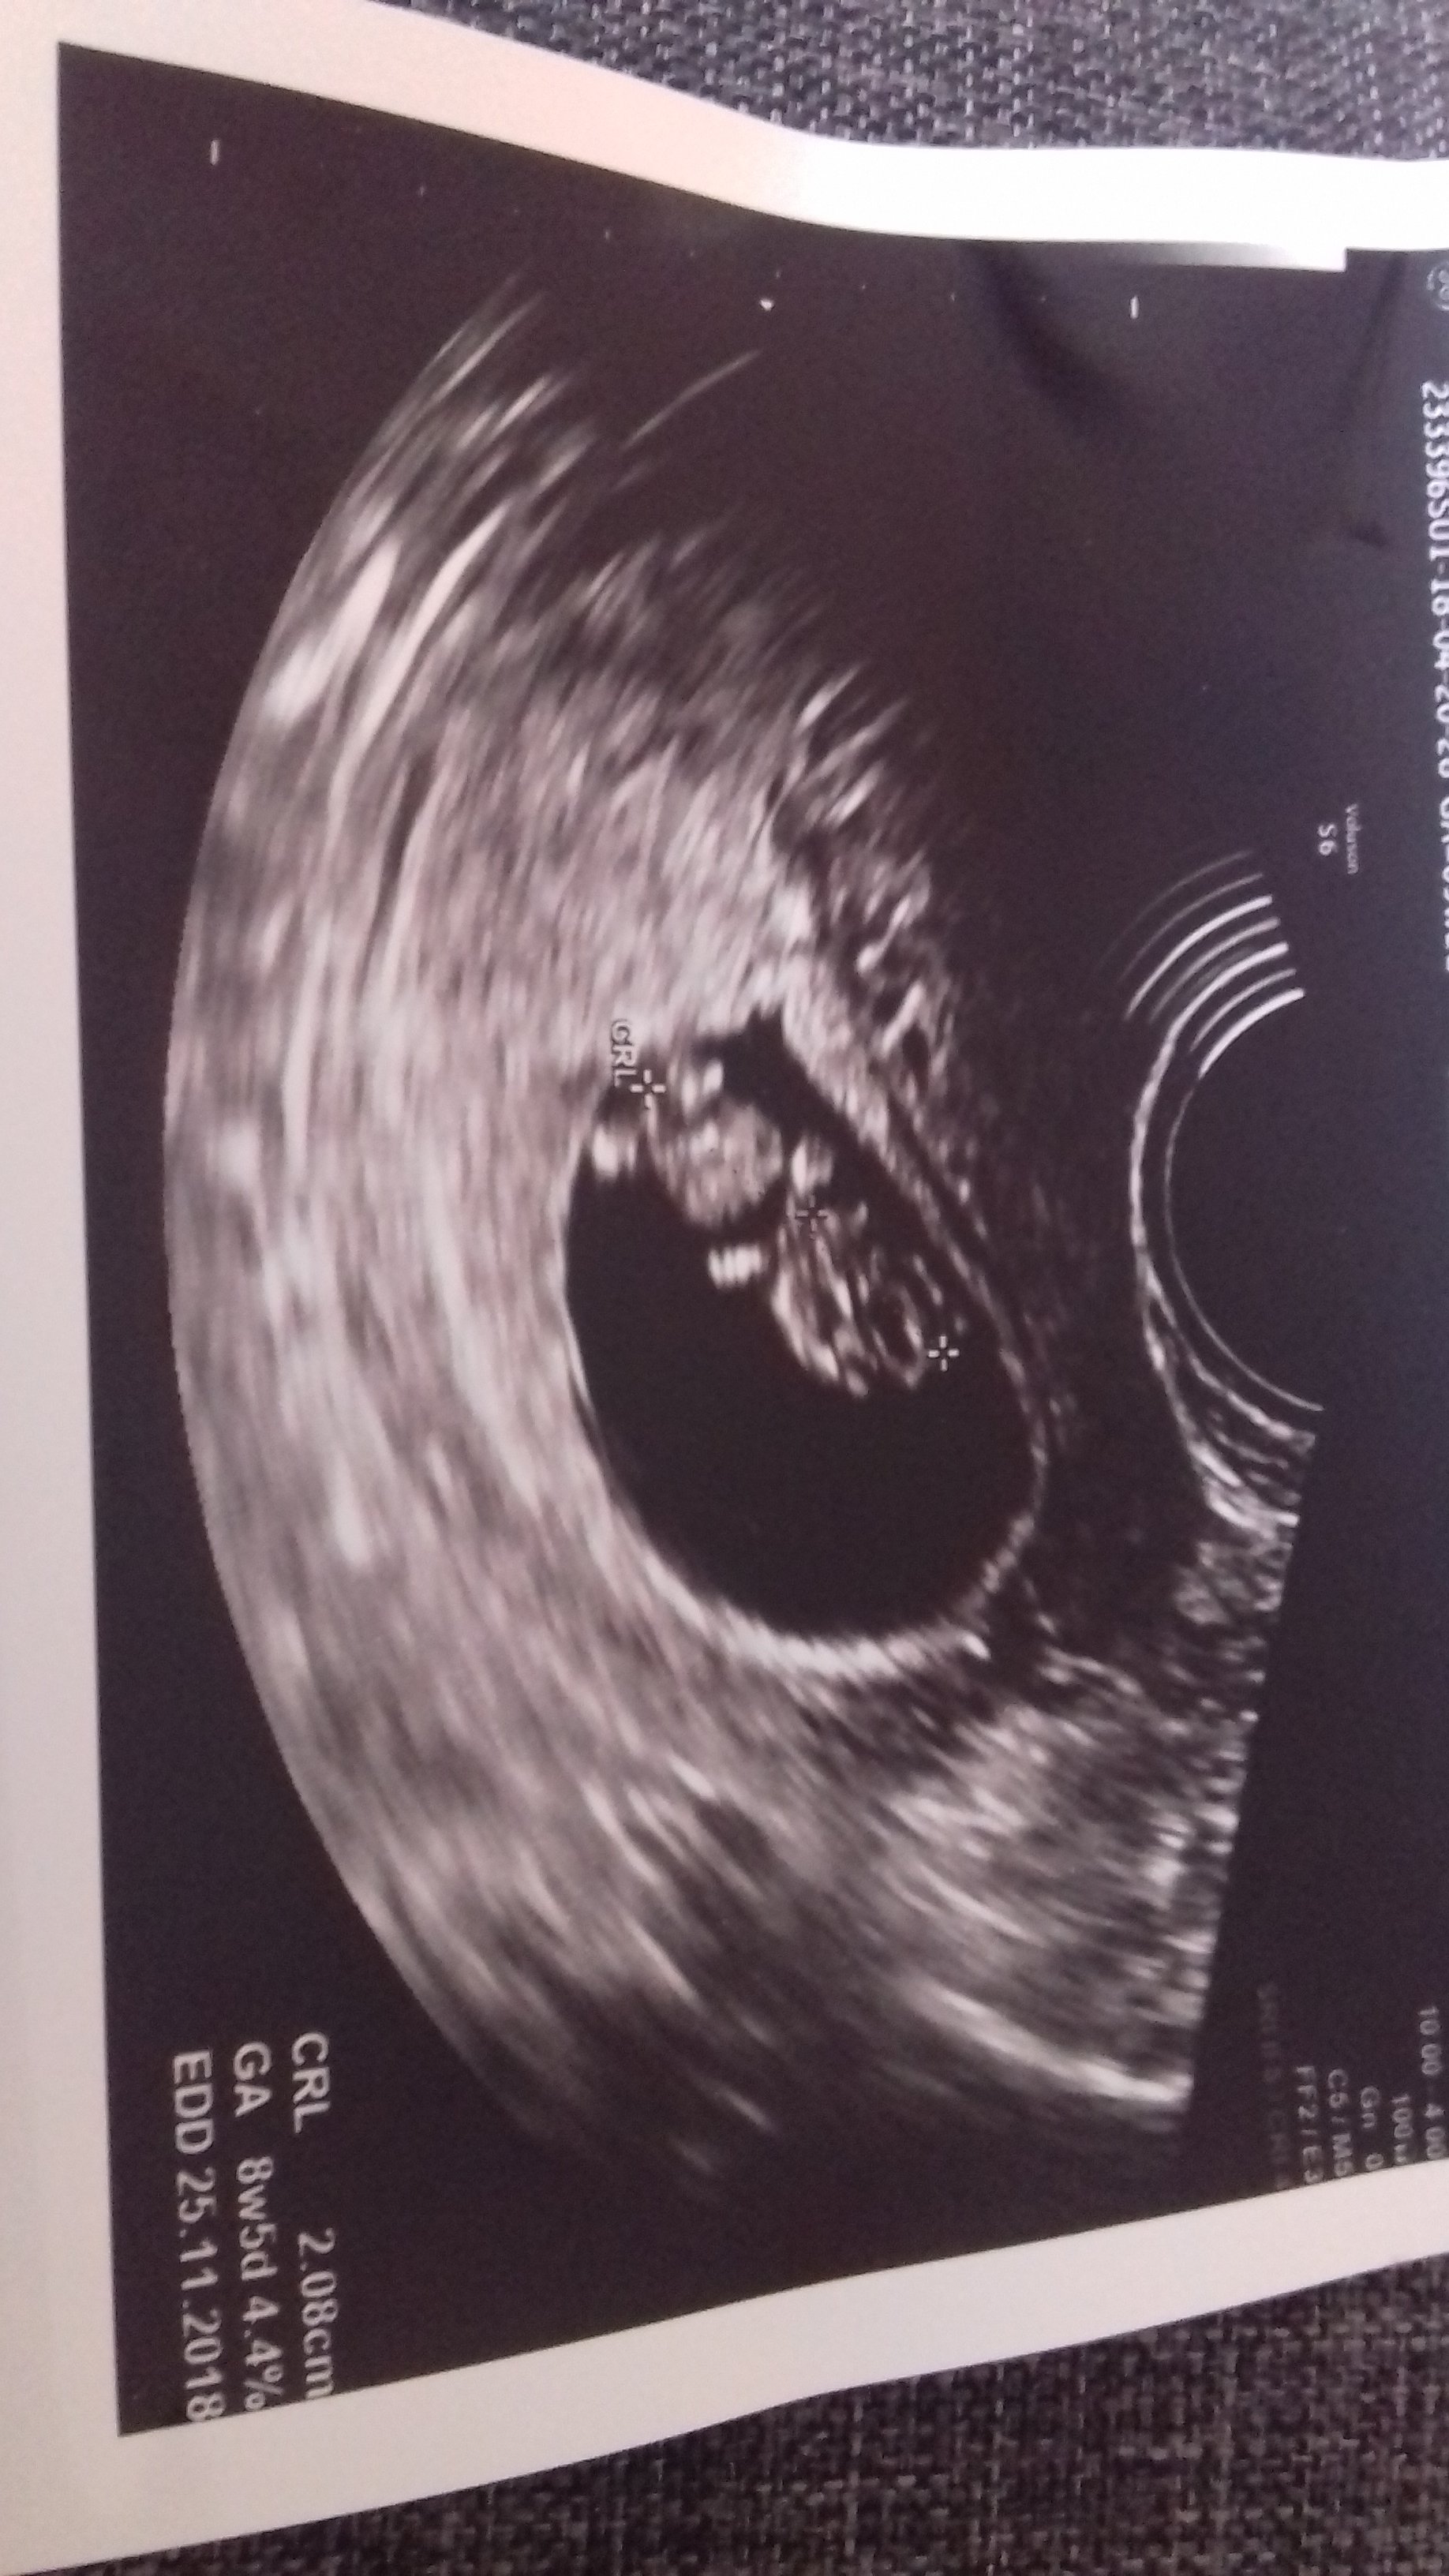

Co do rozbieżności. Nie wiem, może coś lekarz pomylił. Chociaż u mnie jest rozjazd duży między usg a o.m. i on się utrzymuje. Podpytaj i porównaj z następnym usg na wizycie.

Najważniejsze teraz, że serduszko pięknie bije a maleństwo rozwija się.